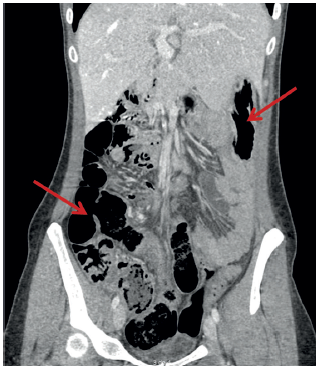

En el Servicio de Urgencias se solicitó una ecografía abdominal, en la cual se observó una lesión quística de 2 cm de diámetro correspondiente a un quiste del uraco e ileítis. Tras dichos hallazgos, la paciente ingresó a cargo del Servicio del Aparato Digestivo donde, dada la ausencia de mejoría del cuadro clínico, se ordenó una tomografía computarizada (TC) de abdomen y pelvis. En la misma, se identificaron cambios inflamatorios de la grasa mesentérica, y la raíz vascular del mesenterio se encontró rodeada por un manguito de tejido, correspondiente a una brida, además del tronco arterial común del que nacen la arteria gástrica izquierda, la hepática y la mesentérica superior, y la vena mesentérica superior que drena en la vena porta izquierda, conformando el signo del remolino (whirlpool sign) 4, y un probable quiste de uraco de 18 mm de diámetro (figuras 1 y 2).

Figura 2. Las flechas señalan el colon en el hemiabdomen derecho y el estómago en el flanco izquierdo; el marco cólico y el ángulo de Treitz no se observan.